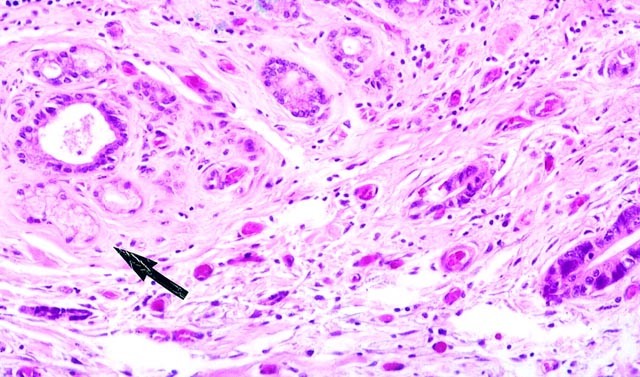

Reactive atypia of the surface epithelium was also a constant feature. The most severe reactive changes were seen in the four cases in which the surgical stents were placed. It occurred more often in the surface epithelium than in the intramural glands. Reactive atypia was characterized by a heterogeneous cell population. Cuboidal and columnar cells with basophilic, clear, or lightly eosinophilic cytoplasm predominated. The nuclei were vesicular or hyperchromatic and contained prominent nucleoli. Mitotic figures were common. Intraepithelial and subepithelial inflammatory cells, consisting predominantly of neutrophils, were nearly always present (Fig. 7). These atypical reactive cells often lead to diagnostic problems, especially in interpreting the common bile duct margin frozen sections in five of our cases. In fact, in one case of foveolar and pyloric gland metaplasia and in another case in which squamous metaplasia was seen as well, the diagnosis of carcinoma was seriously considered in the bile duct brushings because of the presence of reactive atypical cells. Although carcinomas were seen in close proximity to foci of metaplasia, no dysplastic foci were found in the metaplastic glands or within the surface gastric foveolar epithelium (Fig. 8).